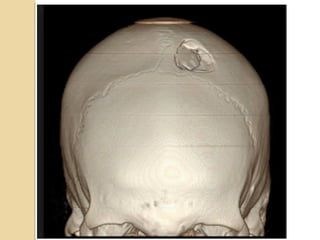

Skull FracturesSkull Fractures

SIGNIFICANT SKULL FRACTURESSIGNIFICANT SKULL FRACTURES

“Depressed”: inner table is depressed by

the thickness of the skull.

Overlie major venous sinus, motor

cortex, middle meningeal artery

Pass through sinuses

Look for sutural diastasis (lambdoid)

Skull FracturesSkull Fractures Thinskull #’s common place. Risk of # associated intracranial injuries? CT to R/o 1. Open 2. Closed 3. Comminuted 4. Diastatic 5. Depressed

SIGNIFICANT SKULL FRACTURESSIGNIFICANTSKULL FRACTURES “Depressed”: inner table is depressed by the thickness of the skull. Overlie major venous sinus, motor cortex, middle meningeal artery Pass through sinuses Look for sutural diastasis (lambdoid)